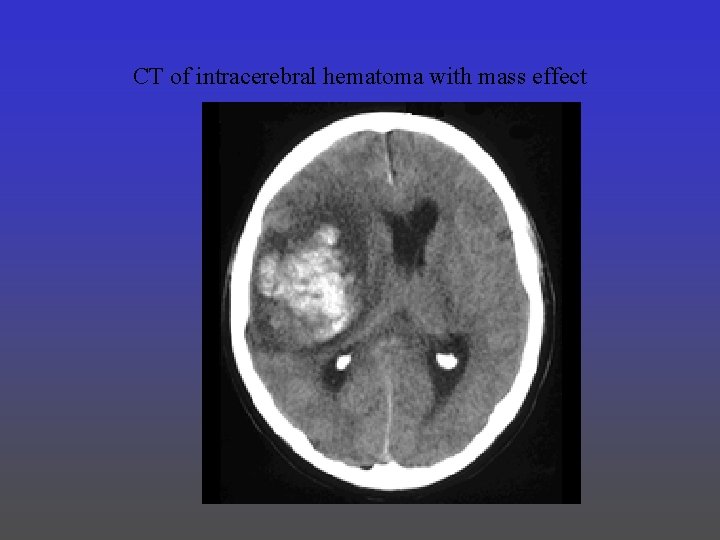

CT of intracerebral hematoma with mass effect